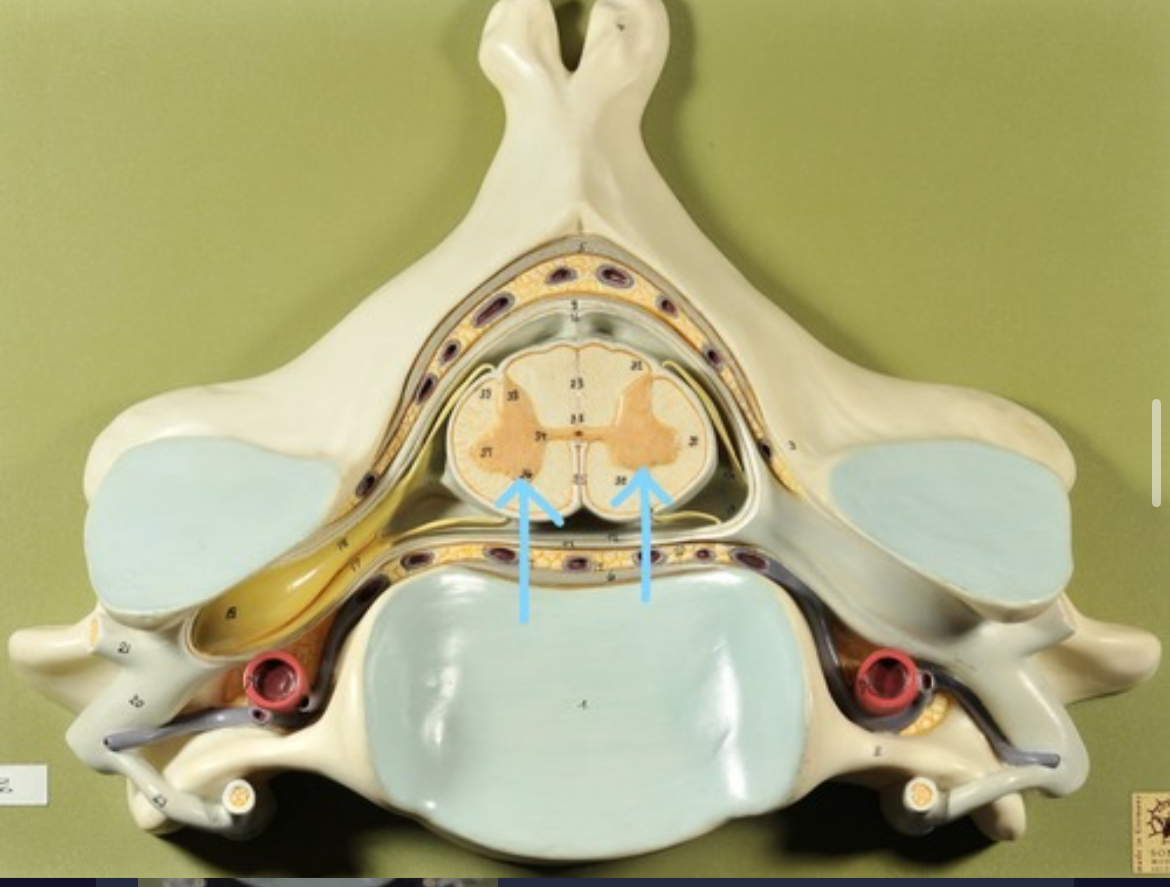

Ventral horns (of gray matter)

Dorsal horns

Anterior columns of white matter

Lateral columns of white matter

Posterior columns of white matter

central canal of spinal cord

Pia matter

Subarachnoid space

Arachnoid matter

Subdural space (brown line)

Dura matter

Epidural space

Dorsal root ganglion

Dorsal root

Ventral root

Spinal nerve